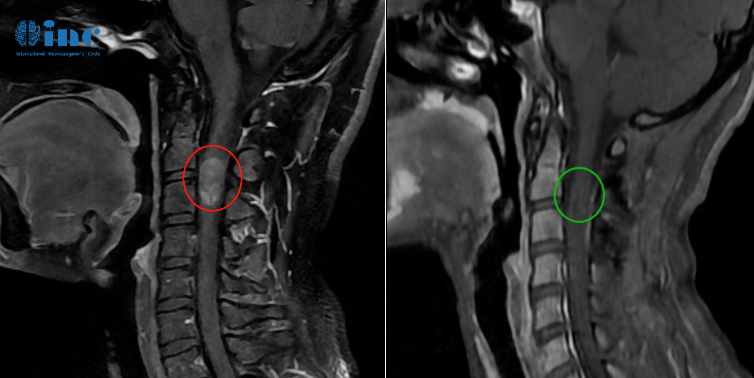

28岁女性-脊髓髓内室管膜瘤

◉手术日期:2022年11月巴教授疑难示范手术期间

◉患者情况:28岁的潇潇2016年前开始出现肩部至腰部疼痛,2020年潇潇肩部后侧疼痛加剧,于当地医院行磁共振检查,提示髓内占位性病变,保守治疗无效。2021年7月行增强磁共振提示C3水平占位,直径7mm。当地医院排除炎性病变。因考虑到手术风险大,未作手术治疗。2021年10月复查磁共振提示影像较前大致相仿。2022年6月磁共振提示大小约8*12*14mm。2022年10月磁共振提示8*12*19mm。

◉治疗过程:2022年12月4日,苏州独墅湖医院,潇潇的手术顺利进行,巴教授顺利全切潇潇脊髓髓内的肿瘤。

◉术后情况:术后一天ICU查房,潇潇已经清醒,意识清楚,四肢能够正常活动。教授表示等到术后二天潇潇就可以转入普通病房,一些不舒服的症状,例如手麻等都是正常的,不属于术后并发症,后期能够恢复正常状态。